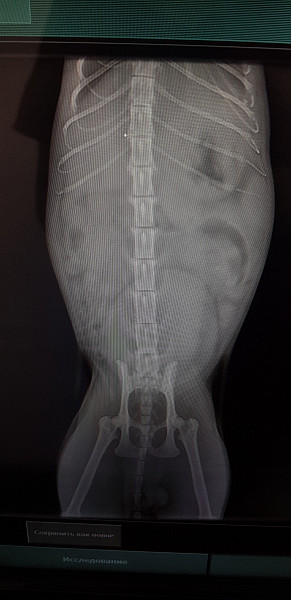

Выполнен рентген брюшной полости. (Снимки прикладываю как фото)